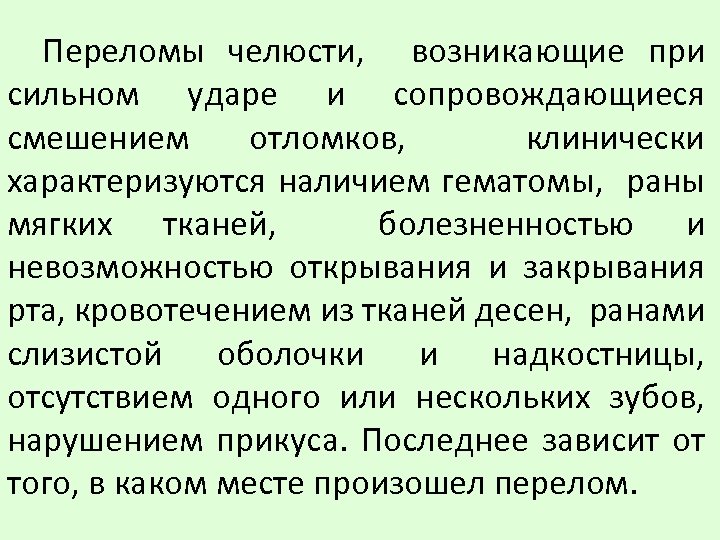

Переломы челюсти, возникающие при сильном ударе и сопровождающиеся смешением отломков, клинически характеризуются наличием гематомы, раны мягких тканей, болезненностью и невозможностью открывания и закрывания рта, кровотечением из тканей десен, ранами слизистой оболочки и надкостницы, отсутствием одного или нескольких зубов, нарушением прикуса. Последнее зависит от того, в каком месте произошел перелом.